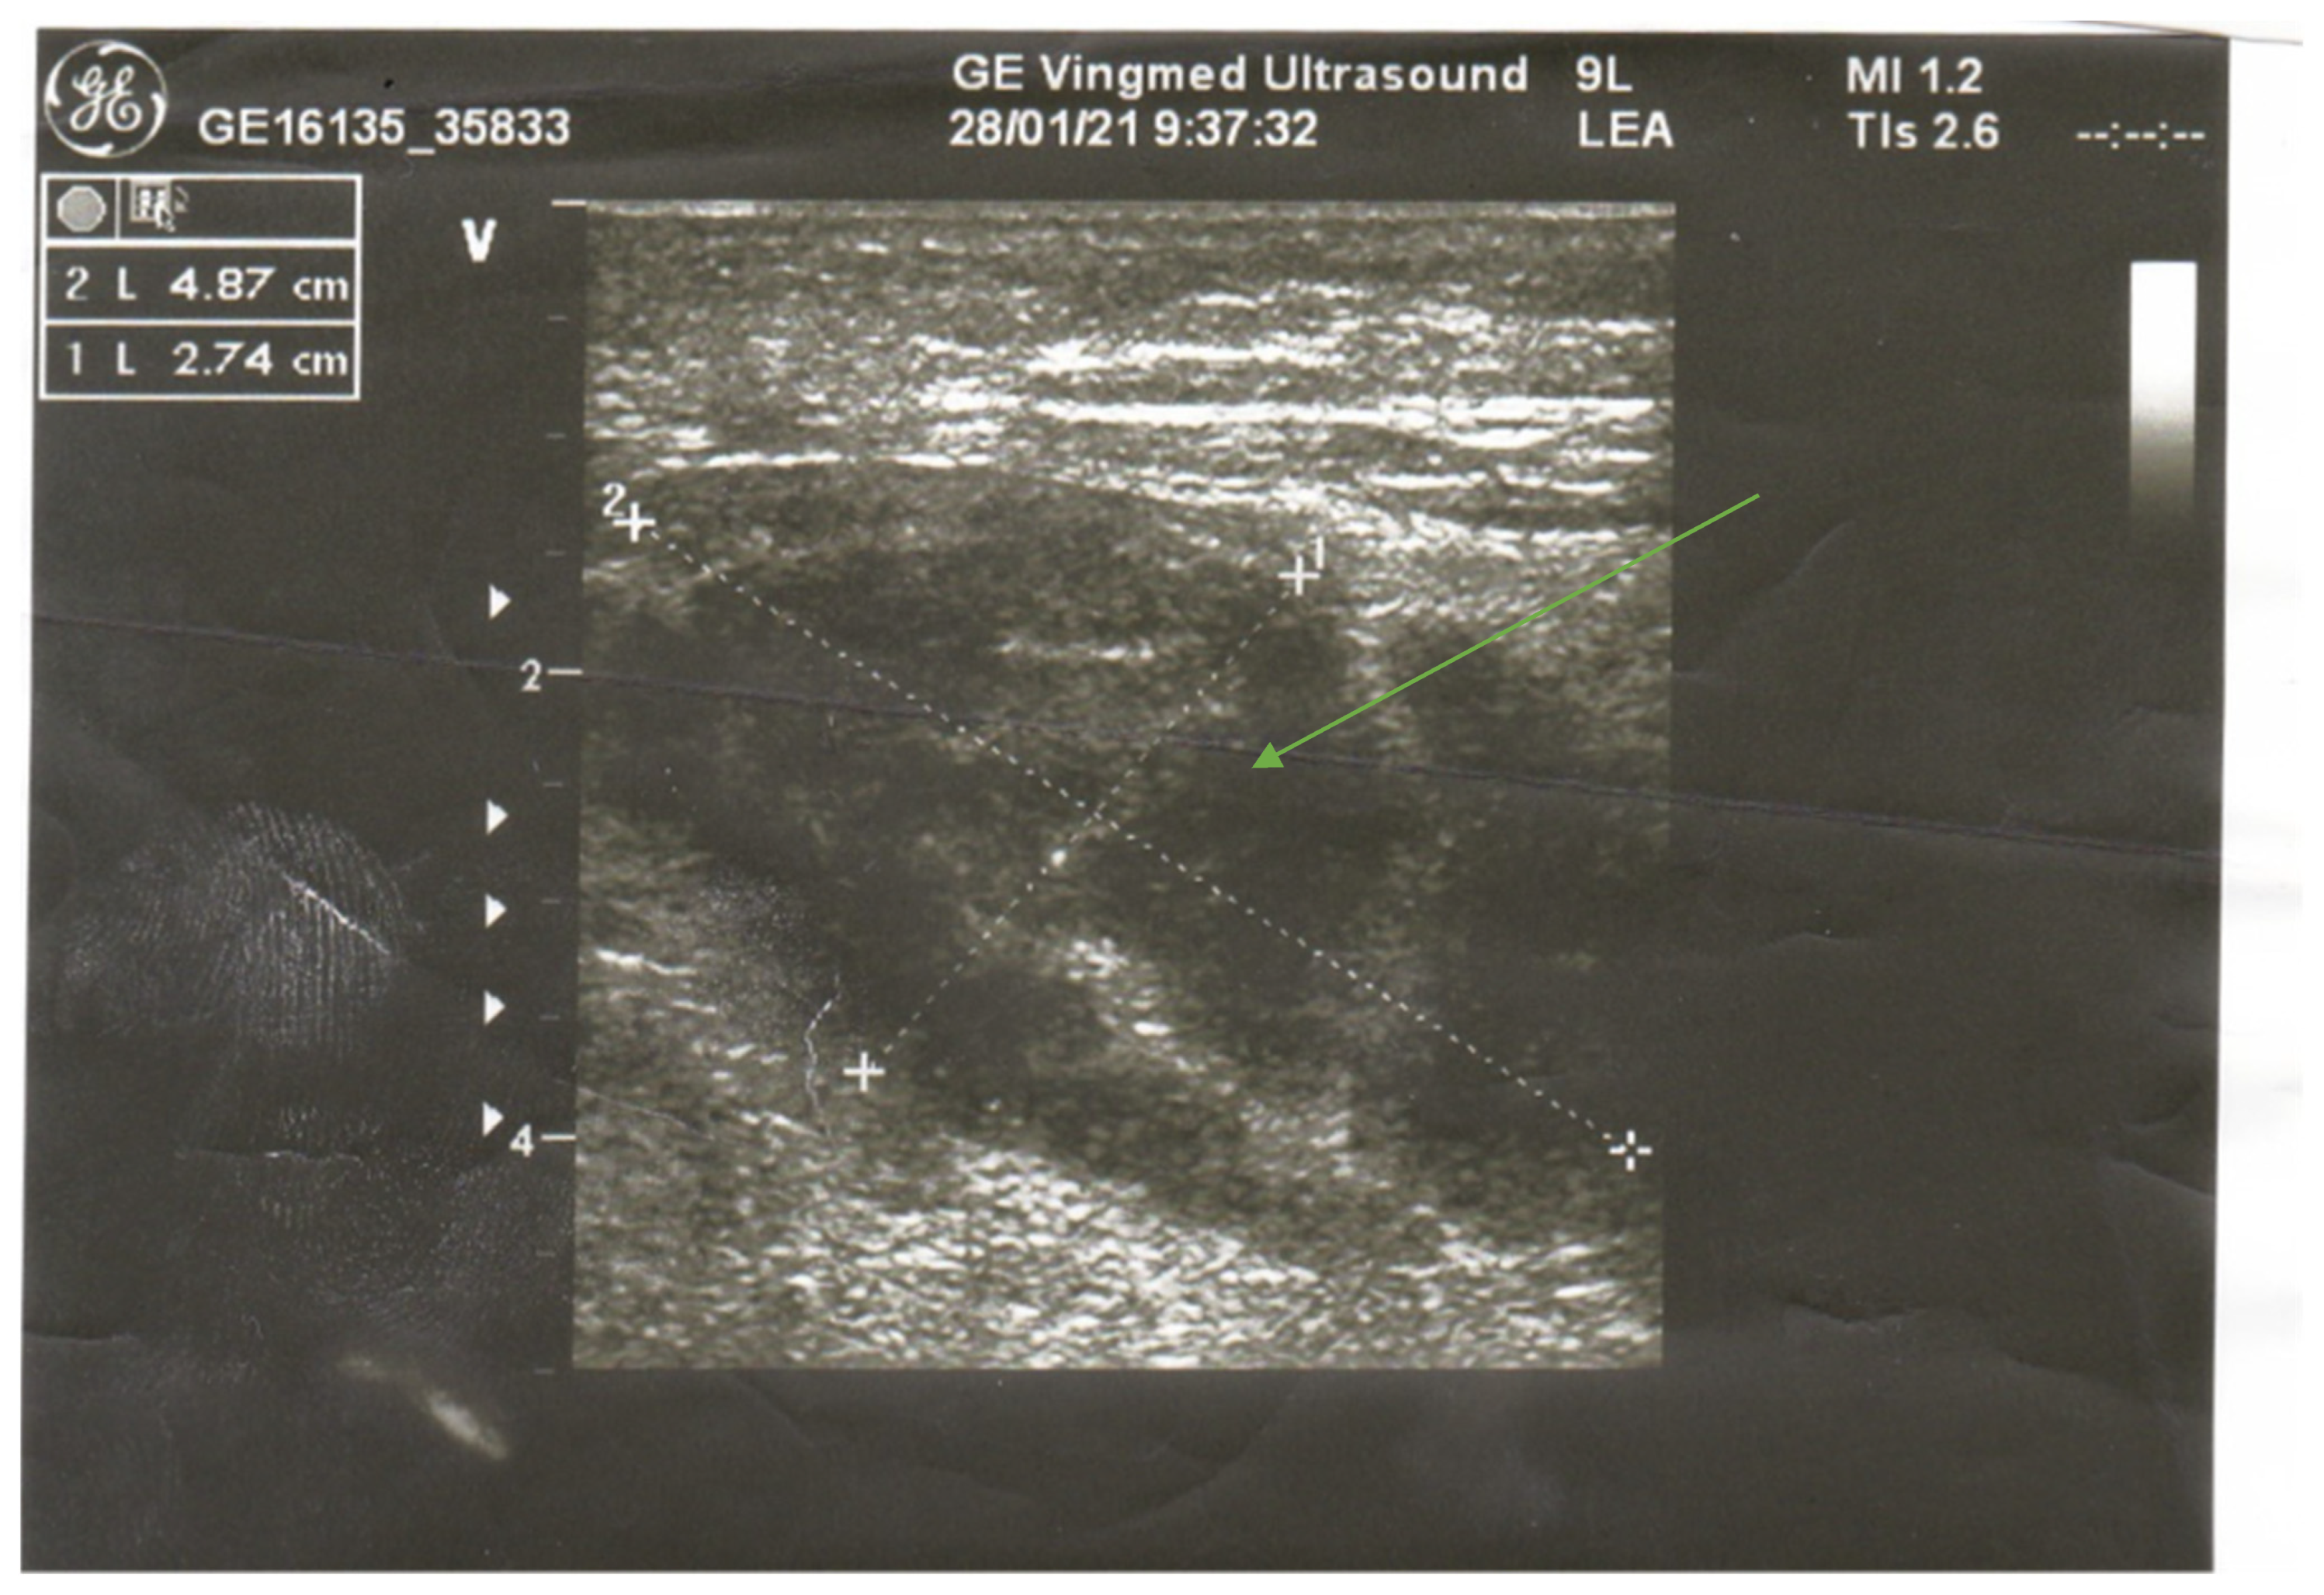

Initially, in the differential diagnosis, we considered focal myositis, abscess, or diabetic muscle infarction; therefore, magnetic resonance imaging (MRI) of the right leg with gadolinium contrast was considered. However, because of end-stage renal disease (ESRD), the nephrologist suggested a computed tomography instead. CT scans revealed an irregular area, not enhanced after contrast administration, located in the short head of the biceps femoris muscle with the size of 2.3 × 2.2 × 8.0 cm accompanied by local subcutaneous edema (Figure 2). The image raised suspicion of abscess or local necrosis. Moreover, lymphadenopathy in the right groin and along external iliac vessels was observed, as well as intramural calcification of arterial walls.

Computed tomography examination is less helpful. In our process of diagnostics, it left us with more questions than answers, but usually it may serve to exclude local abscesses, tumors, or bone destruction. The axial unenhanced CT image shows diffuse muscular enlargement with low attenuation, increased attenuation of the subcutaneous fat, and thickening of subcutaneous fascial planes and of the skin. After contrast administration, CT reveals a low-attenuation lesion with ring-enhancing margins in the involved muscle [7,11,12].

Figure 2. Right thigh CT after contrast administration revealed the fluid collection of degradation in posterior muscle compartment—arrow.